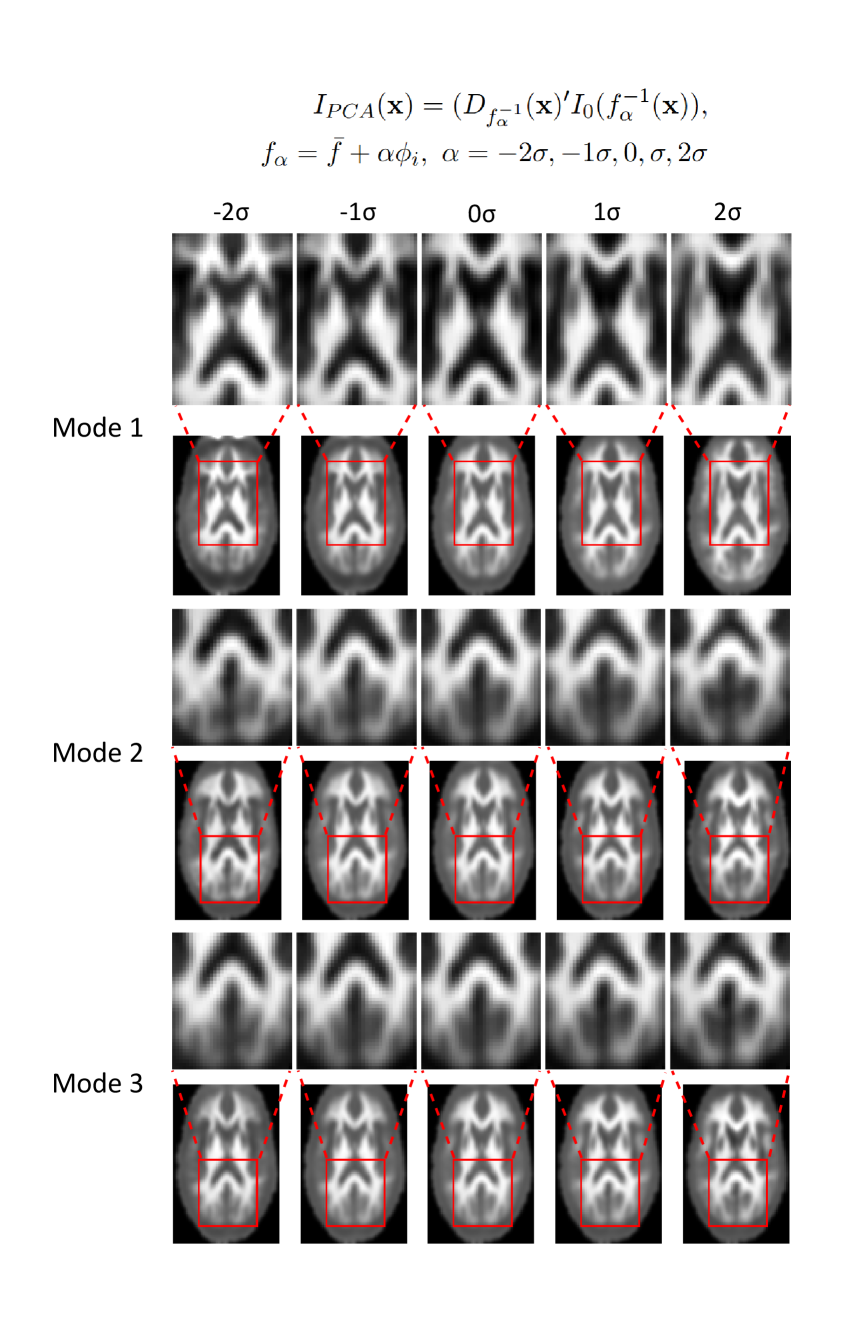

Refer to caption

Figure 5: Image variations along the first three principal component directions derived from PCA.

Visualizing the results of PCA helps to observe the distribution and characteristics of the data. The component vectors {ϕ1,ϕ2,,ϕk}\{\phi_{1},\phi_{2},...,\phi_{k}\} obtained from Equation (6) capture the most representative directions of the data distribution. By sampling data points along these directions and mapping them back to the transport domain, the distributional characteristics of the data set can be visualized in an intuitive and interpretable manner(Equation (8)).

IPCA(𝐱)=(Dfα1(𝐱)I0(fα1(𝐱)),\displaystyle I_{PCA}(\mathbf{x})=(D_{f_{\alpha}^{-1}}(\mathbf{x})^{\prime}I_{0}(f_{\alpha}^{-1}(\mathbf{x})), (8)

fα=f¯+αϕi,α=2σ,1σ,0,σ,2σ\displaystyle f_{\alpha}=\bar{f}+\alpha\phi_{i},\ \alpha=-2\sigma,-1\sigma,0,\sigma,2\sigma

where σ\sigma is the standard deviation of PCA loadings for component vectors ϕi\phi_{i}. Figure 5 illustrates the variations of the images along the first three principal components obtained by PCA according to Equation (8).